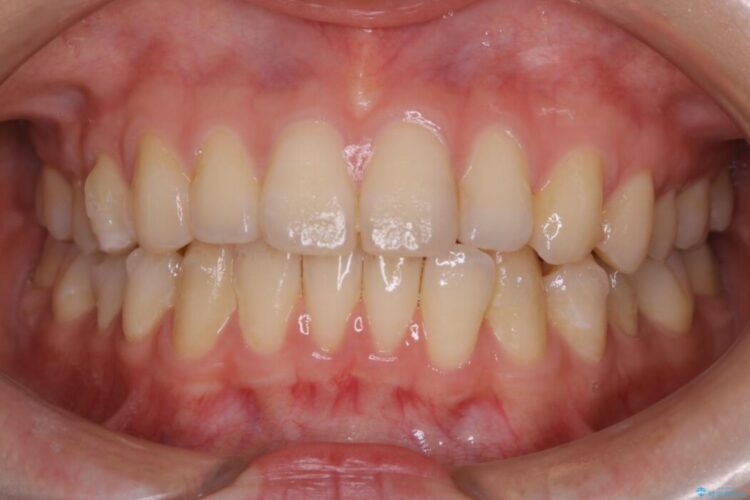

- 治療期間:6ヶ月

- 矯正装置:インビザライン ライトパッケージ

通常の全体矯正と比べピンポイントの部分矯正となると、動かす歯が少なくなるため治療期間が格段に短くなり、費用が抑えられることがメリットとして挙げられます。